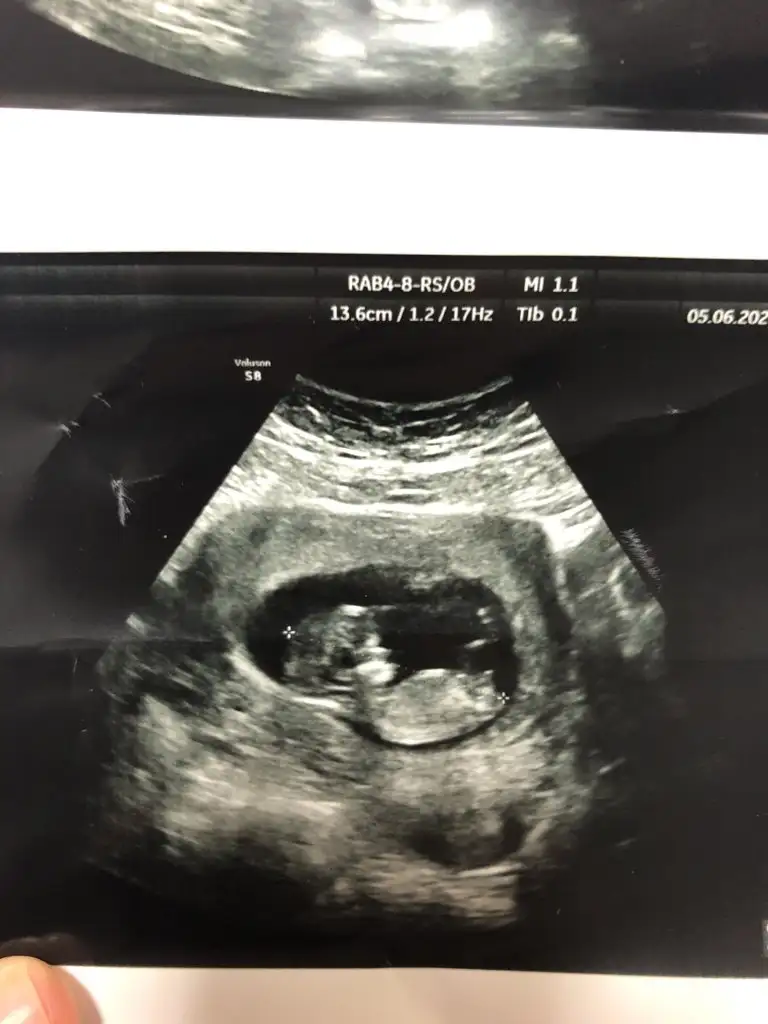

bu da diger acidan fotografi ayagi kapatmis gibi amabu bu haftaki goruntusu 12. hafta gecen hafta erkek demistiniz ama emin olamamistiniz@ikrameyra

Mrb 13 haftalik olduk cok sukurKız gibi net de değil kız sanki 12-13 olunca tekrar usg paylaşın

Kız gibiMrb 13 haftalik olduk cok sukur

Kız gibi